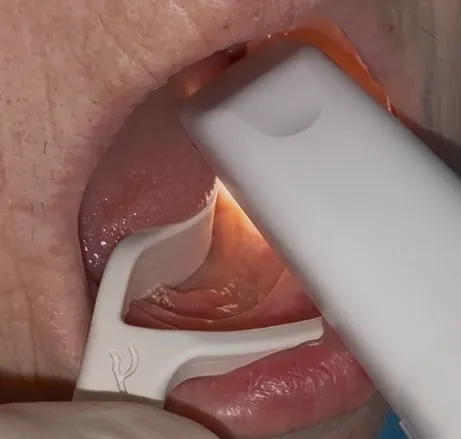

• Scansione intraorale di arcate edentule

• Flussi digitali per riabilitazioni implantari estese

• Stabilizzazione dei tessuti molli e controllo dei movimenti involontari